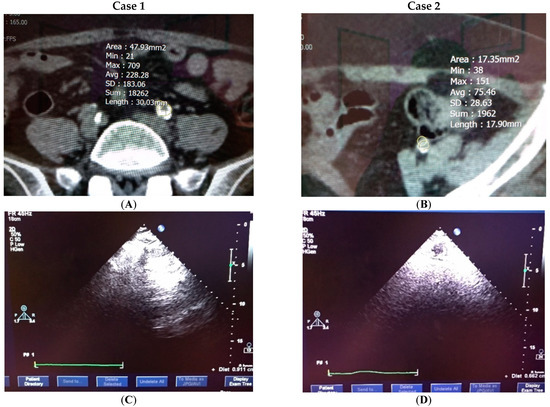

4.4. Clinical Testification